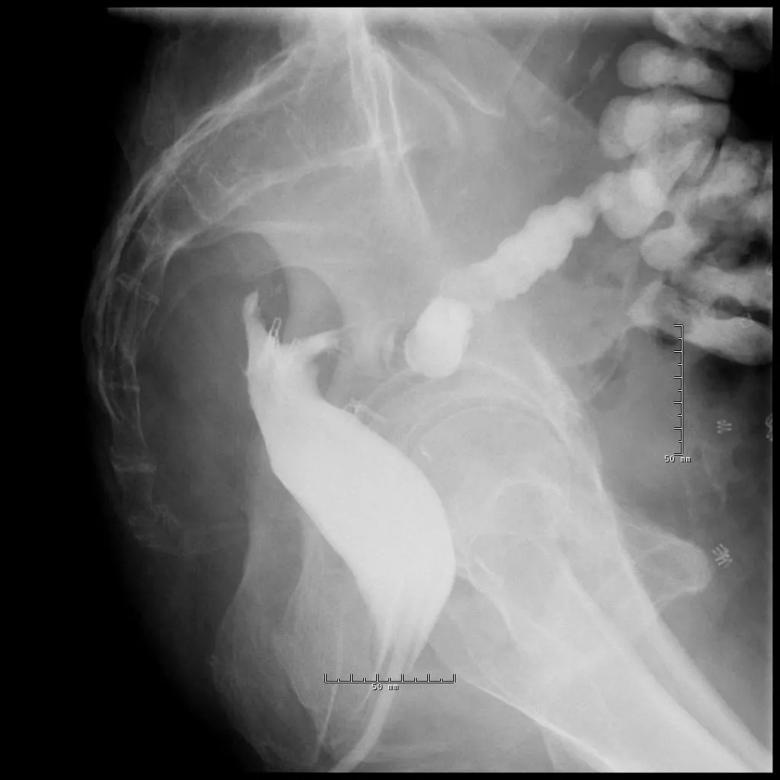

The long sinus track from the anastomosis.

Treated sinus track, almost resolved.

Subsequently, the presacral sinus was completely healed with two sessions of endoscopic sinusotomy with isolated knife tip (see main image above), which was pioneered at Cleveland Clinic. Each session of this outpatient endoscopic procedure took 15 minutes with the patient under conscious sedation. The recovery time for each procedure was 30 minutes.